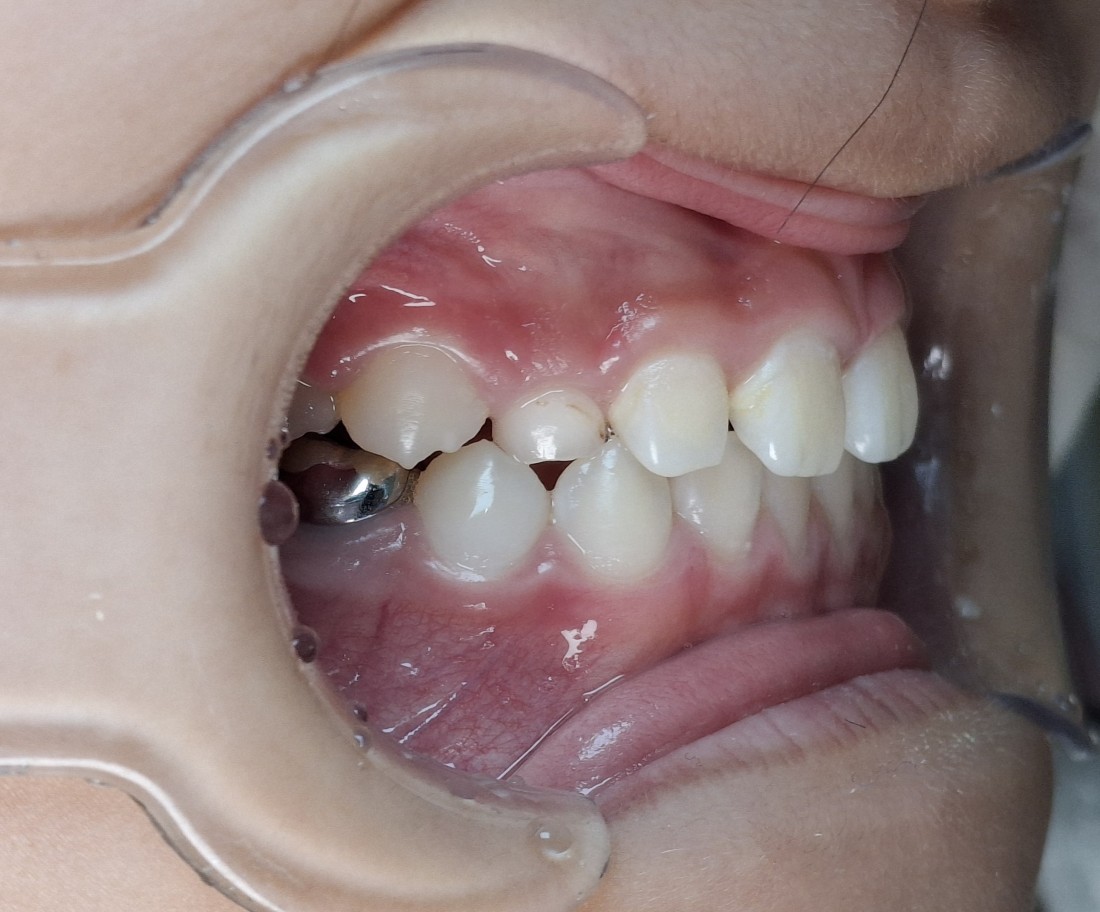

프리올소 교정장치는

현재 서울대학교 소아치과 교정과,

연세대학교 소아치과 교정과에서

교수님들이 정말 많은 빈도로 처방하고 있는

소아부정교합 개선 방법입니다.

광주 부정교합 치과 중에서는

서울우리아이치과에서

광주/전남 프리올소 사용량 1위 치과로

굉장히 많은 케이스를 다루고 있으며,

성공적인 소아부정교합 개선 사례를

많이 공유해드리고 있습니다.